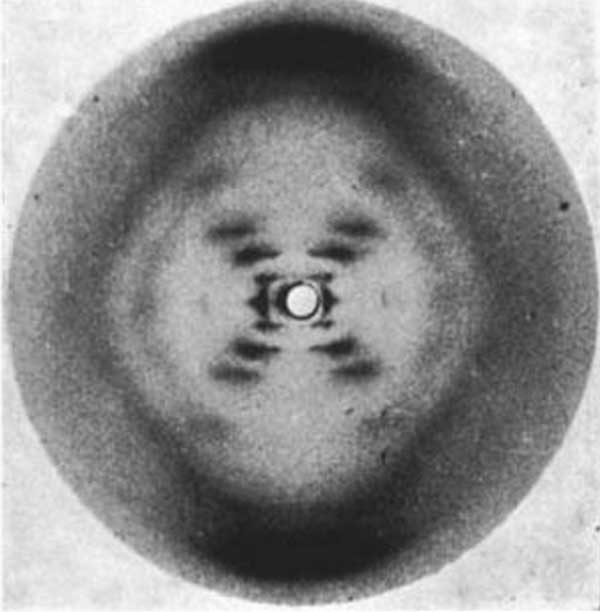

‘ক্রায়ো-ইএমে’র চোখে দেখা প্রোটিন অণু

ক্রায়ো-ইএমের চোখ দিয়ে দেখা টেট্রাসাইক্লিন রেজিস্ট্যান্স প্রোটিনের মতো জটিল অণু

সরল প্রোটিন অণুর ক্রায়ো-ইএম (সিঙ্গল পার্টিক্ল ক্রায়ো-ইএম)

এক্স-রে ক্রিস্টালোগ্র্যাফিতে যে ভাবে দেখা হয় প্রোটিন কেলাস

এক্স-রে ক্রিস্টালোগ্র্যাফিতে যে ভাবে দেখা হয় প্রোটিন কেলাস